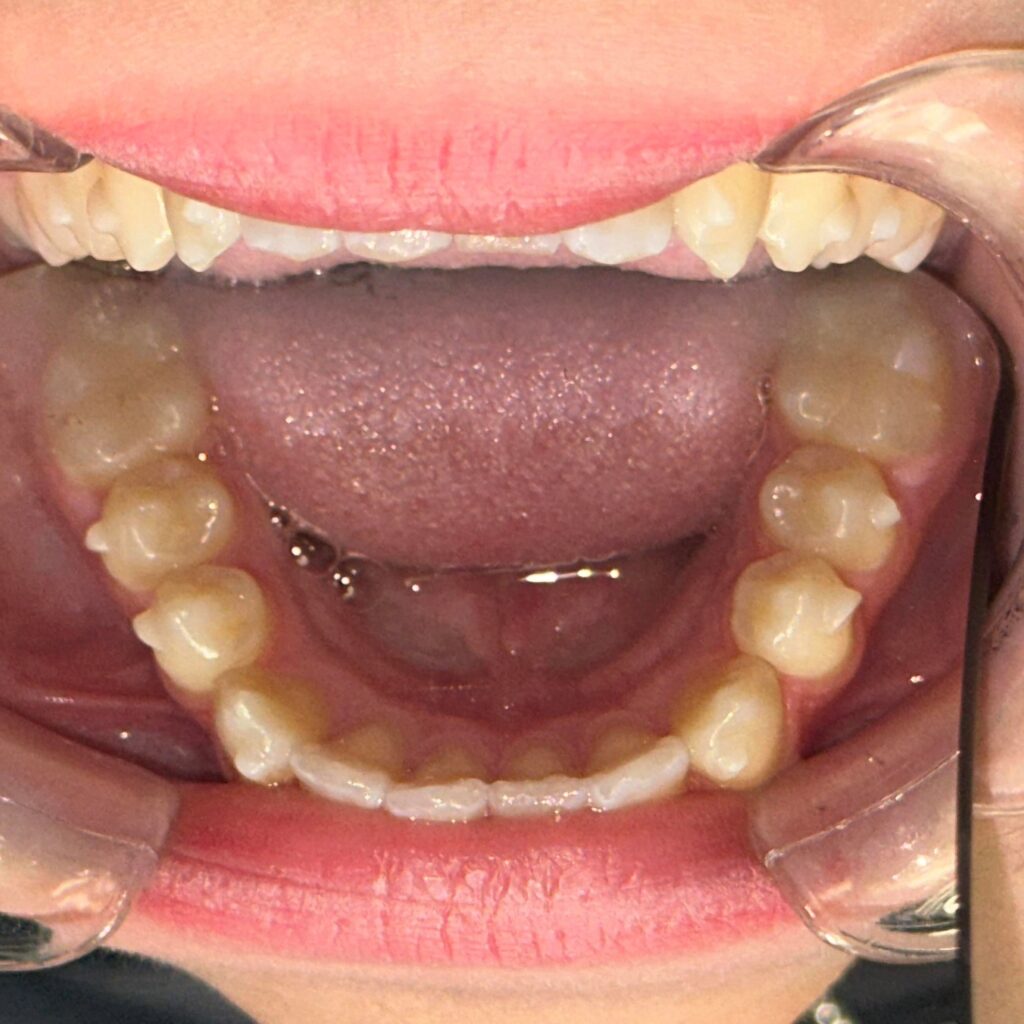

- wykonania precyzyjnego plan leczenia oraz indywidualnych skanów zębów Pacjenta skanerem wewnątrzustnym,

- umiejscowieniu na zębach przezroczystych zaczepów i nałożeniu pierwszego setu nakładek